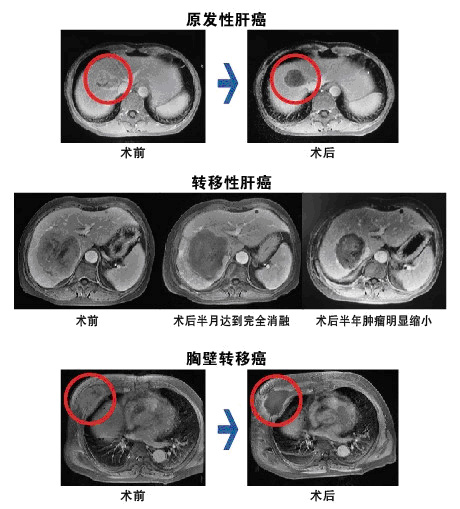

典型病例

劉小北,大連市友誼醫(yī)院超聲消融腫瘤治療中心主任,腫瘤外科主任,主任醫(yī)師,遼寧醫(yī)學(xué)會(huì)肝病學(xué)會(huì)委員,大連醫(yī)科大學(xué)兼職教授,大連市醫(yī)療事故專家?guī)斐蓡T。長期從事肝膽外科、腫瘤外科的臨床、教學(xué)及科研工作,擅長消化道腫瘤的診斷和外科治療。曾親赴重慶海扶HIFU國際培訓(xùn)基地,專門學(xué)習(xí)高強(qiáng)度聚焦超聲治療腫瘤的新技術(shù)。目前已完成近100余例良、惡性腫瘤的超聲消融治療,病種涉及原發(fā)性肝癌、轉(zhuǎn)移性肝癌、胰腺癌、胸腹壁轉(zhuǎn)移癌、腹膜后腫瘤、盆腔腹膜后巨大腫瘤、子宮肌瘤、子宮腺肌癥(瘤)等。